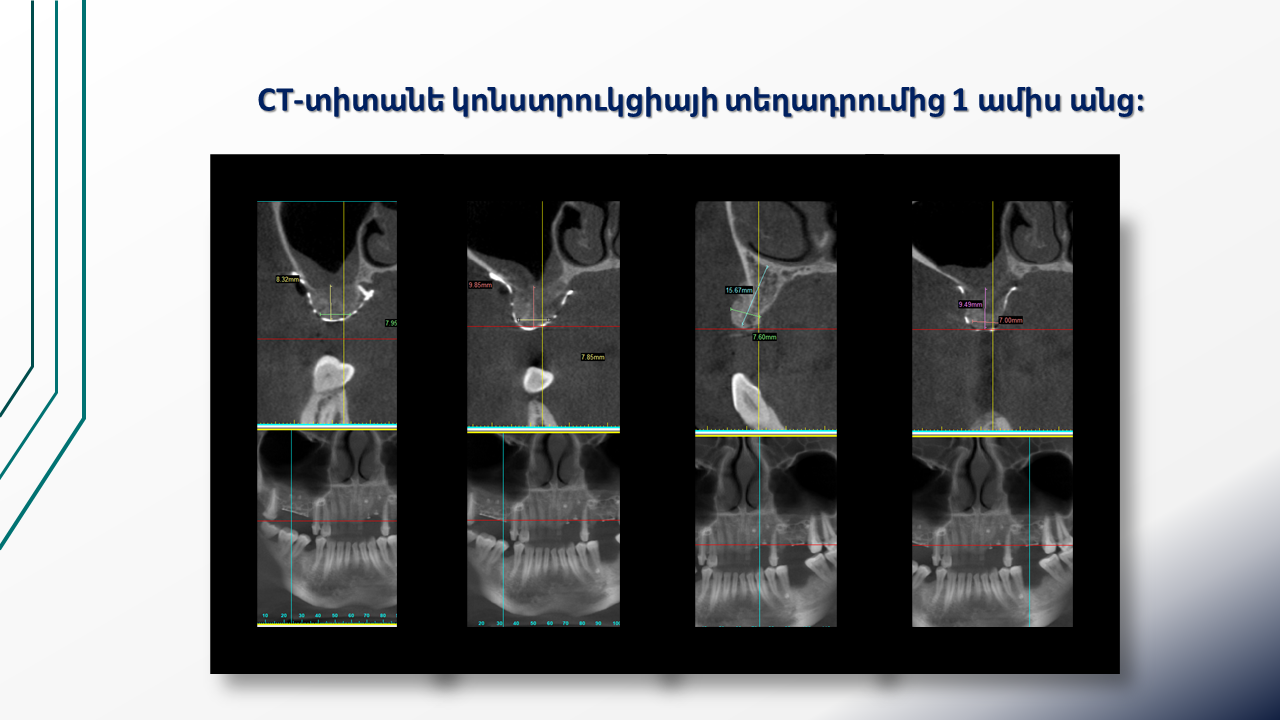

Titanium Mesh for Alveolar Ridge Reconstruction (16.03.2024 )

Clinical case of guided bone regeneration using a patient-specific 3D-printed titanium mesh in a pregnant patient. Multistage protocol with bone augmentation, implant placement, and soft tissue management. Presented by Dr. Levon Galstyan and Dr. Roza Hovhannisyan.